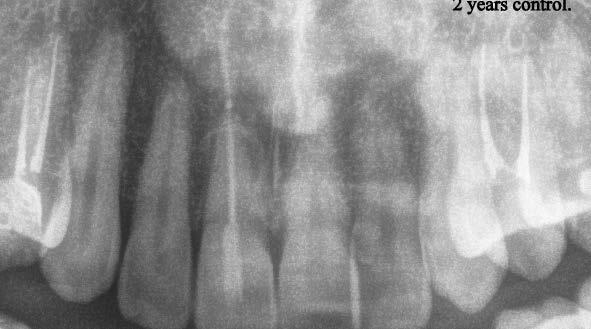

Gyökéramputációt főként a furkáció érintett nagyőrlő fogak ellátása során szoktunk alkalmazni. Derks és mtsai. vizsgálatában a gyökéramputált nagyőrlő fogak közel 80%-a 20 évvel a beavatkozás elvégzését követően is megtartott volt. 1998 októberében egy 39 éves férfi páciens a jobb alsó kvadránsban jelentkező ínyérzékenység miatt kereste fel rendelőnket. A klinikai vizsgálat során jobb alsó első és második nagyőrlő fog között (46–47) nagy kiterjedésű csontveszteséget észleltünk. Ettől eltekintve a teljes fogazat parodontális státusza megfelelőnek bizonyult. A jobb alsó kvadránsban végzett szenzibilitás vizsgálat során arra az eredménye jutottunk, hogy a 46-os fog vélelmezhetően elhalt (10. ábra).

A pácienst tájékoztattuk, hogy az endo-paro léziókkal rendelkező fogak alapvetően rossz prognózissal rendelkeznek.

A kezelés hosszú távú sikeressége nagymértékben függ a csontveszteség mértékétől, a megmaradó gyökércsonk hosszától, a gyökerek közti távolságtól, a rezekálni kívánt

gyökér görbületétől, a csontos defektus megszüntetésének sikerességétől, a fogbél állapotától, és a szükséges restauratív és szájhigiénés beavatkozások elvégzésétől.

A páciens beleegyezését követően a 46-os fog disztális gyökere, a disztális gyökér felett lévő koronális rész megőrzése mellett rezekcióra került (11. ábra). A rezekciót követően a referáló orvos a 46. és 47. fogak koronáját Ribbond szalag és kompozit segítségével egymáshoz rögzítette. A sebészi beavatkozást követően 22 évvel készült kontrollfelvételen a lézió csontos telődése, kortikális csontállomány kialakulása, valamint a furkáció körüli csontos regeneráció volt megfigyelhető (12. ábra) A károsodott fogak megtartására szolgáló lehetőségek fejlődésének, valamint az implantátumok behelyezésével kapcsolatos rizikófaktorok jobb megértésének köszönhetően ma már más szemmel vizsgáljuk a fogak eltávolításának szükségességét. A kérdéses prognózissal vagy a kis protetikai értékkel rendelkező fogak eltávolítása előtt mindig érdemes felmérni az ezzel elérhető lehetséges előnyök nagyságát. A kemény- és lágyszöveti pótlás lehetőségeinek fejlődésével, a PRF elérhetőségével, a minimálinvazív sebészeti módszerek és az operációs mikroszkópok elterjedésével, valamint a varróanyagok és varrat technikák egyre kifinomultabbá válásával ma már alaposan el kell gondolkodnunk az előtt, hogy egy fogat egy implantátum behelyezése érdekében eltávolítsunk. Mára sokkal kedvezőbb prognózist és sokkal nagyobb sikerességet tudunk elérni a korábban menthetetlennek gondolt fogak kezelése során.